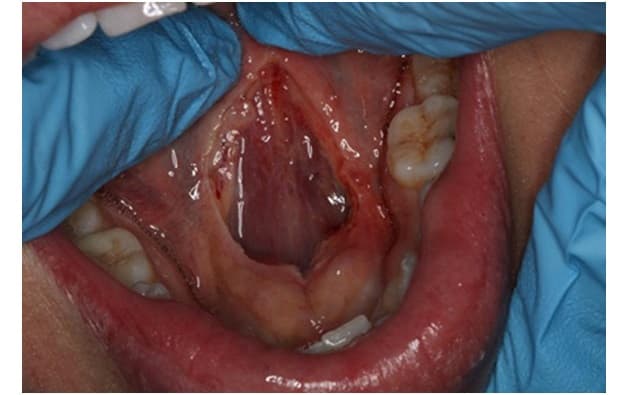

Mô tả phẫu thuật cắt thắng lưỡi

Để có thể phẫu thuật dính phanh lưỡi, người bệnh cần được thực hiện gây mê trong suốt quá trình thực hiện. Về cơ bản, phẫu thuật cắt thắng lưỡi là cắt tấm niêm mạc nối sàn miệng và mặt dưới lưỡi. Song thực tế, trừ một số trường hợp phanh lưỡi chỉ dính ở đầu lưỡi (dính phanh lưỡi nhẹ) thì hầu hết ở người lớn vùng niêm mạc này thường rất rộng và có sự liên kết phức tạp với các mạch máu, dây thần kinh, vì vậy mà quá trình cắt thắng lưỡi cần được thực hiện rất thận trọng.

Song song với cắt phanh lưỡi, bác sĩ cần tiến hành tạo hình vùng dưới lưỡi đồng thời để đảm bảo thẩm mĩ cho vùng dưới lưỡi, và đặc biệt là giúp lưỡi được hoạt động hoàn toàn bình thường, sau phẫu thuật không tạo nên các hố, kẽ nhỏ gây khó chịu cho người bệnh